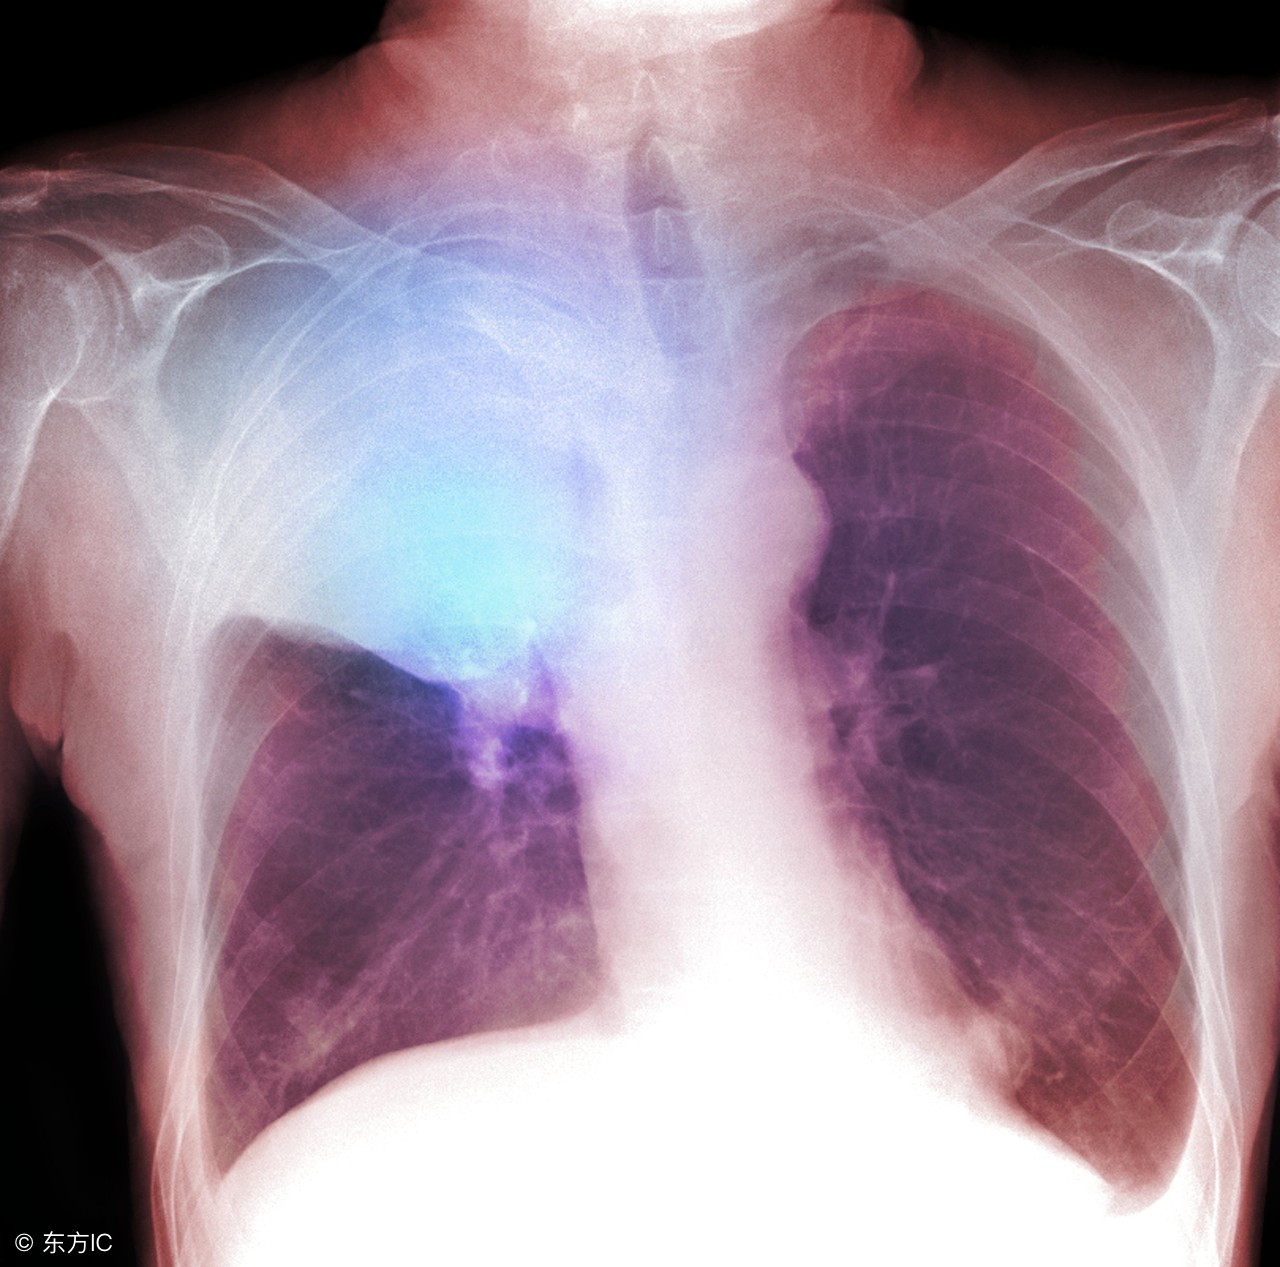

肺癌复发症状是怎样的?癌症是一种让人谈之色变的疾病,它不仅严重威胁人们的生命,还具有很高的复发率,因此肺癌患者手术成功后也可能存在复发的可能。那么肺癌复发症状是怎样的呢?

肺癌复发症状是怎样的?